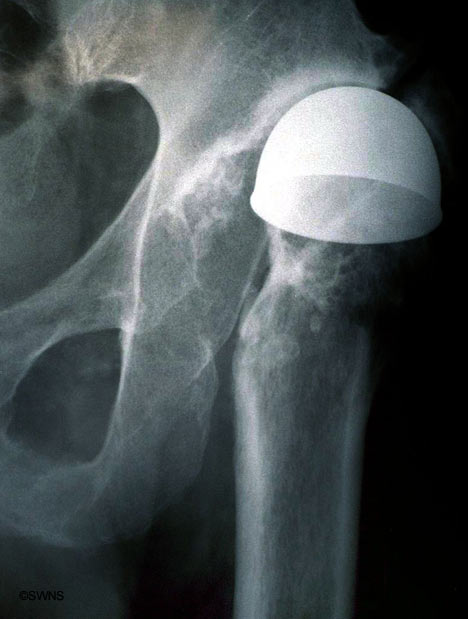

Эндопротез тазобедренного сустава.

Уважаемые коллеги! Вот такой вот рисурфейс. Что делать? Какой прогноз выживаемости эндопротеза?